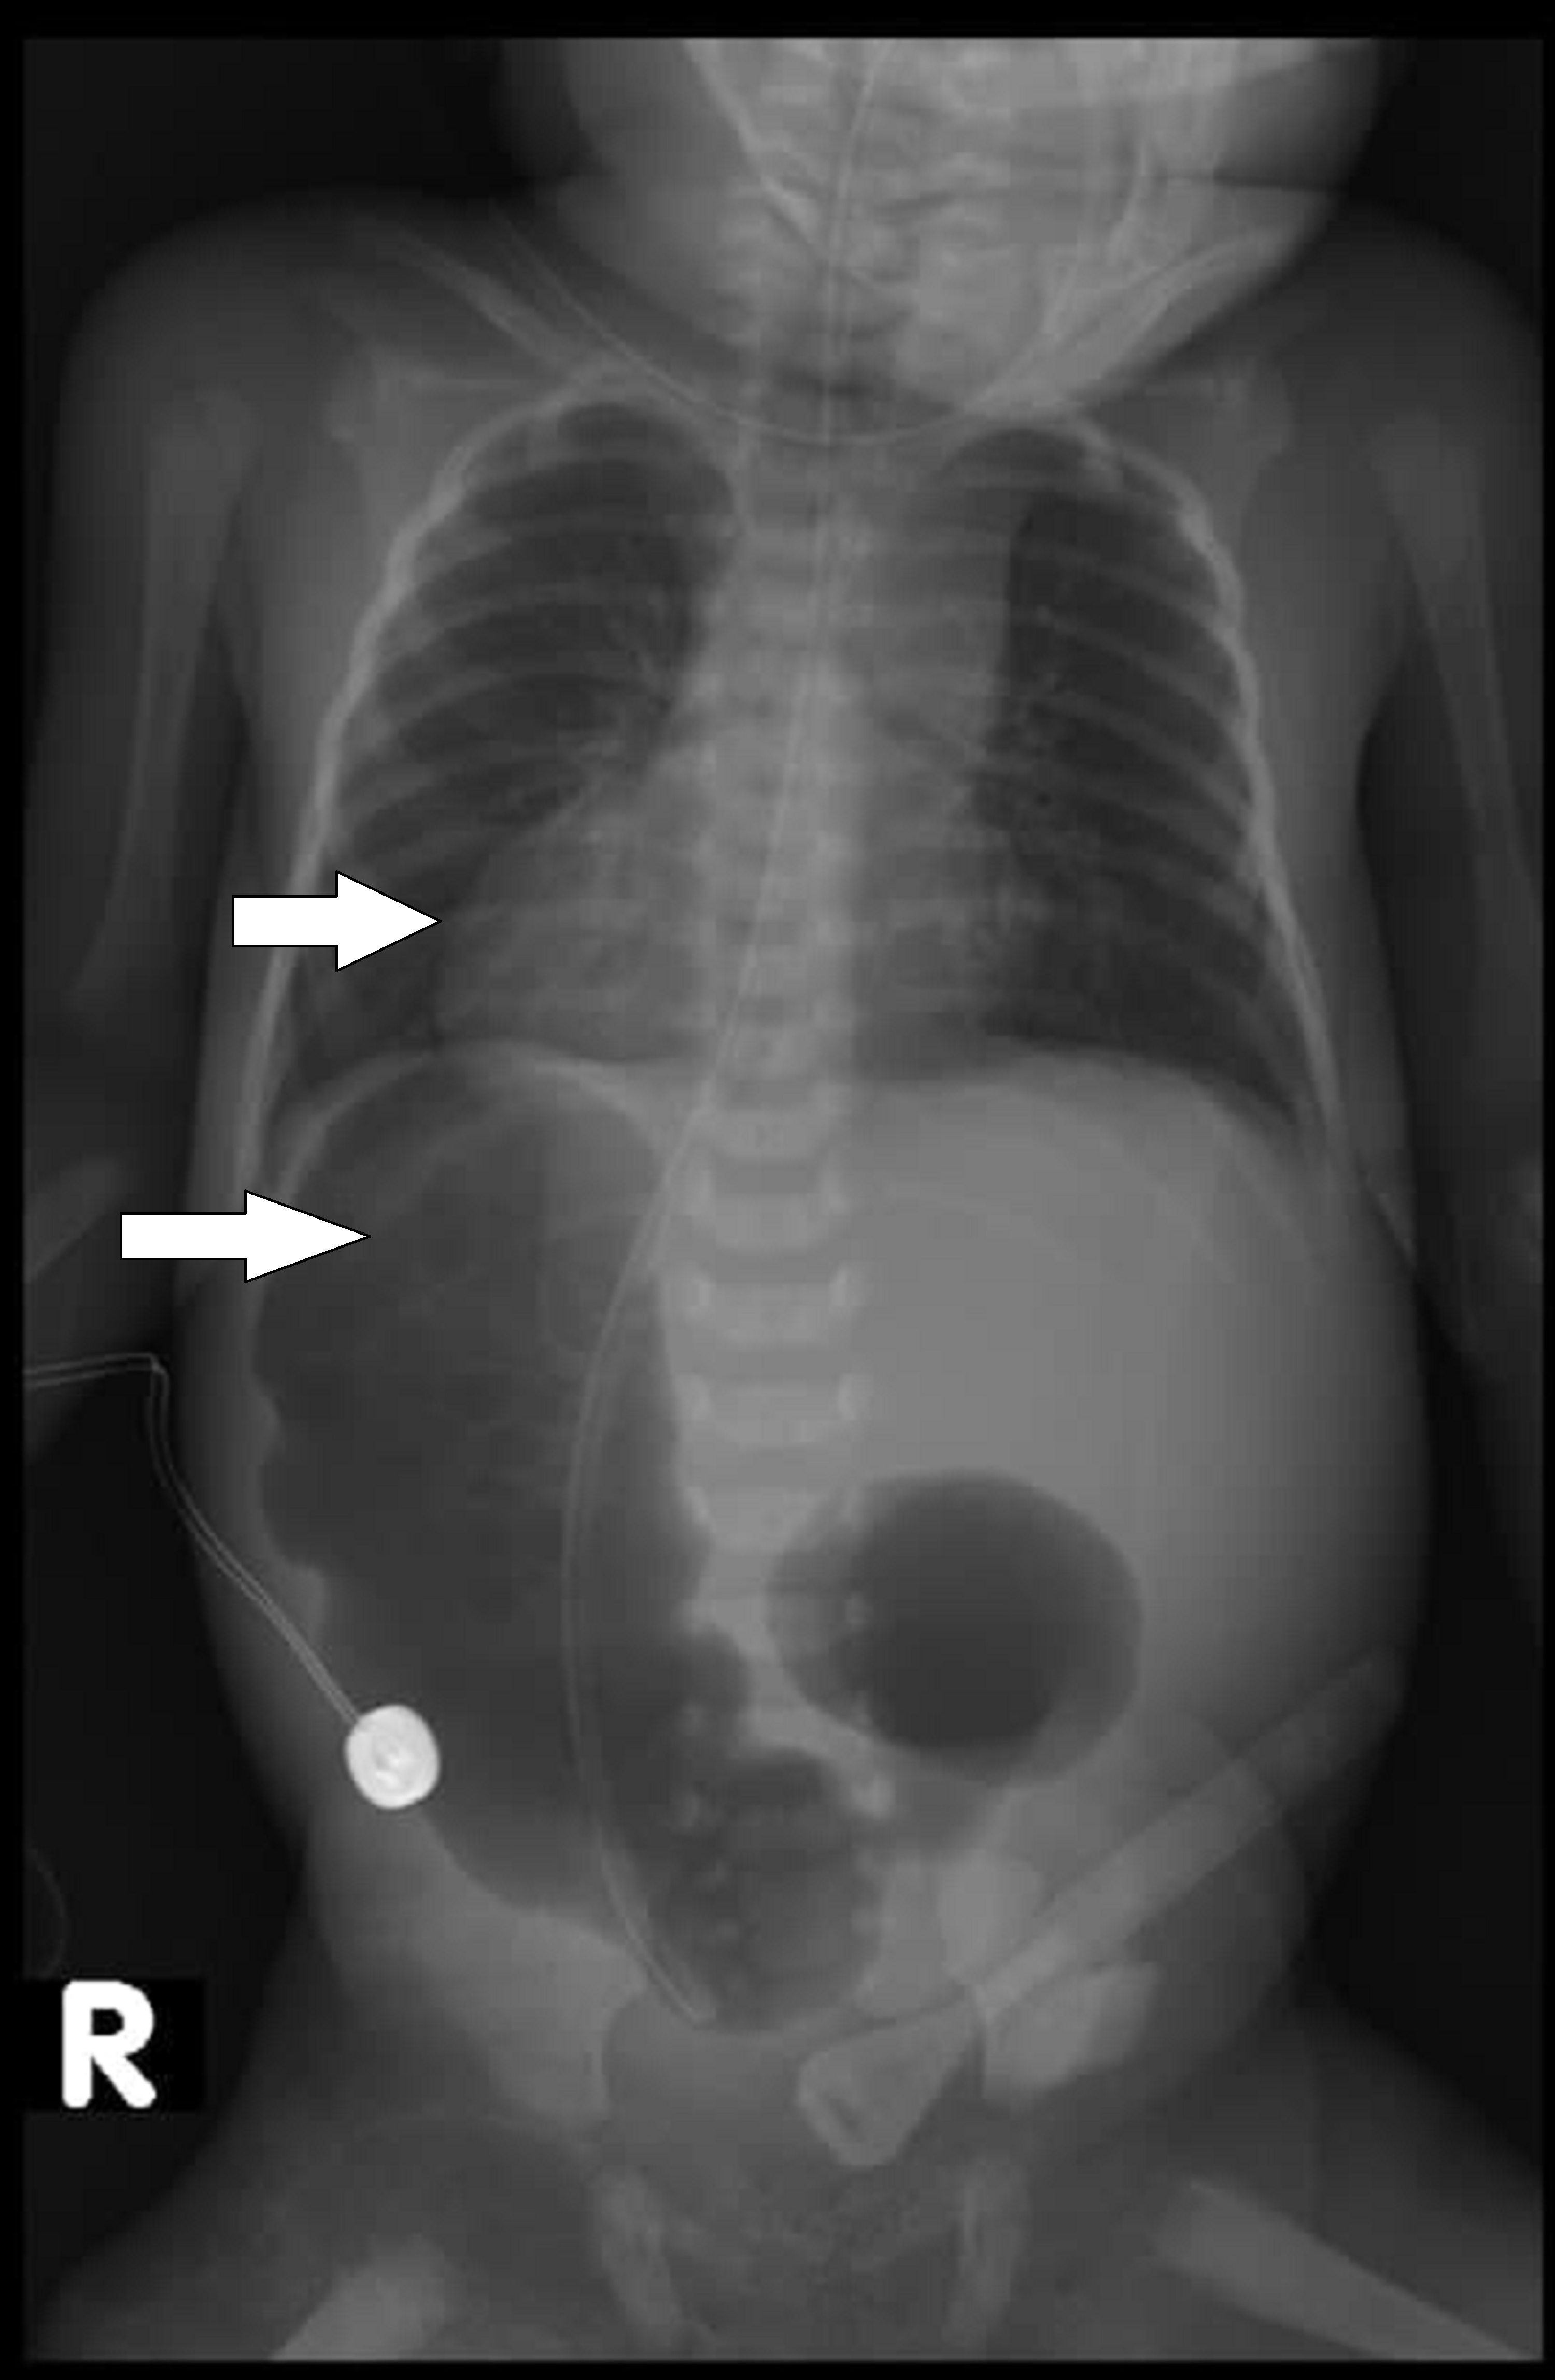

Situs Inversus

This condition is where someone is born with their organs on the opposite side of the body to what they are supposed to be. For example, the heart is on the right or below the stomach. This usually doesn't need to be treated and is passed down through family genes.